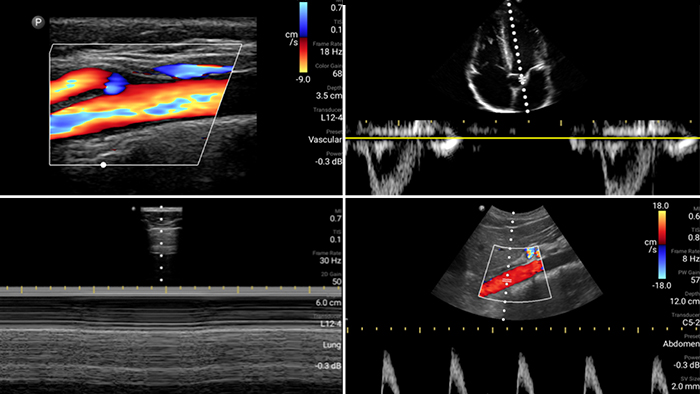

Lumify is with you

every step of the way

Evaluate, diagnose and treat your patients in

minutes with a multi-point POCUS exam.

See more when it counts

From revealing the subtle details of an image to uncovering enriched tissue definition from multiple angles, Lumify can help you make real-time decisions with more confidence from assessment through recovery.